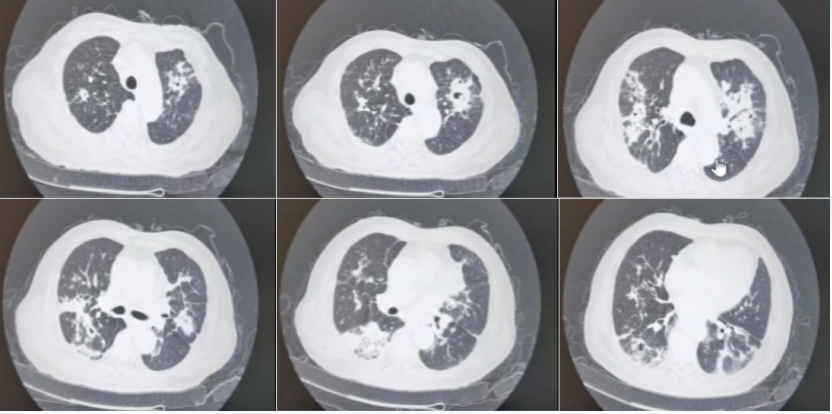

• 入院后胸部增强CT(2022-08-10)肺部结节样病变和空洞样病变较前明显进展(图2)

2  患者胸部增强CT(2022-08-10)